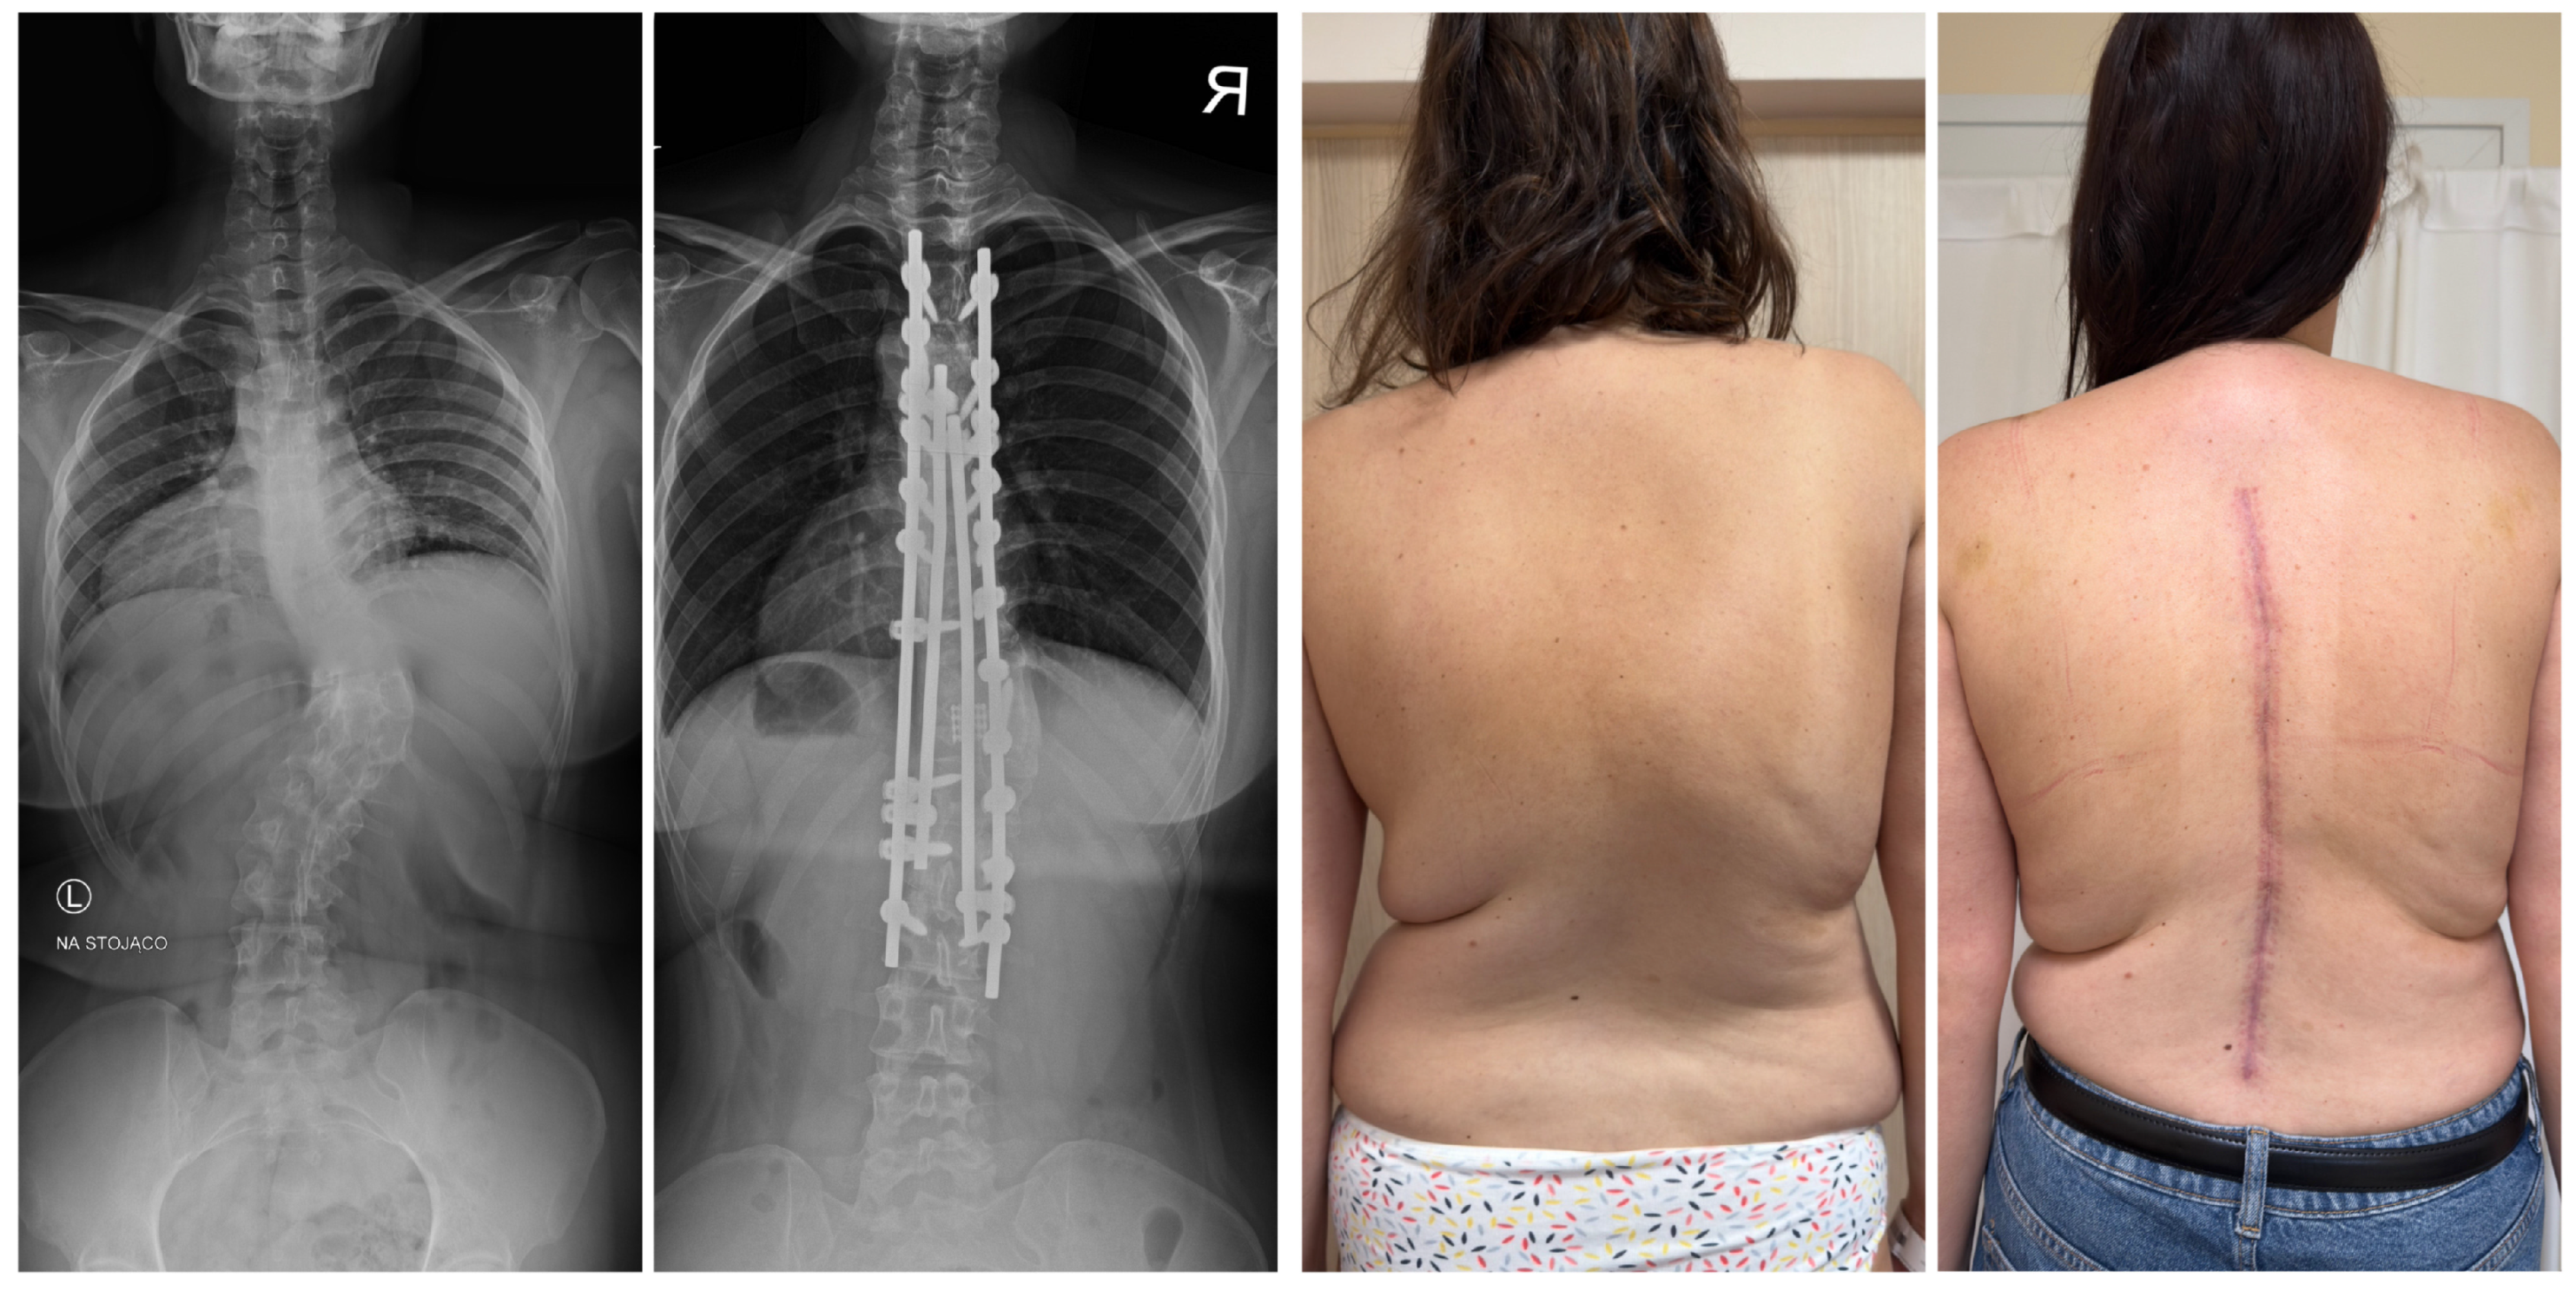

7.3. Surgical Techniques

7.3.3. Hemivertebrectomy

7.3.4. Growing Rod Systems